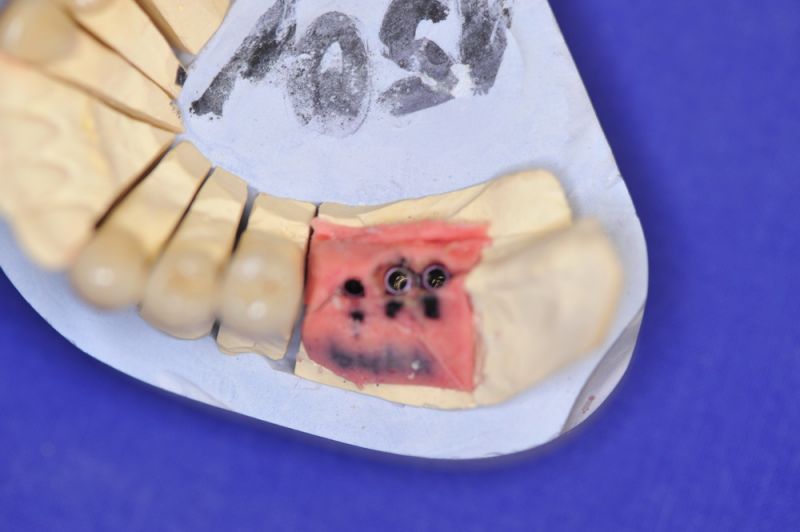

3. Sehr dünne Implantate, die von ursprünglich zwei je Kieferhälfte auf letztendlich drei je Kieferhälfte umgeplant werden mussten.

4. Notwendigkeit die Mundhygienefähigkeit der Arbeit auch unter sehr beengten Verhältnissen zu schaffen, um der Arbeit eine günstige Prognose mitzugeben.

1. Notwendigkeit eines professionellen regelmäßigen Recalls, alle drei Monate

2. Notwendigkeit der Intrerdentalraumhygiene. Zwischen den Zähnen einmal pro Tag. Zwischen den Implantataufbauten zweimal pro Tag.